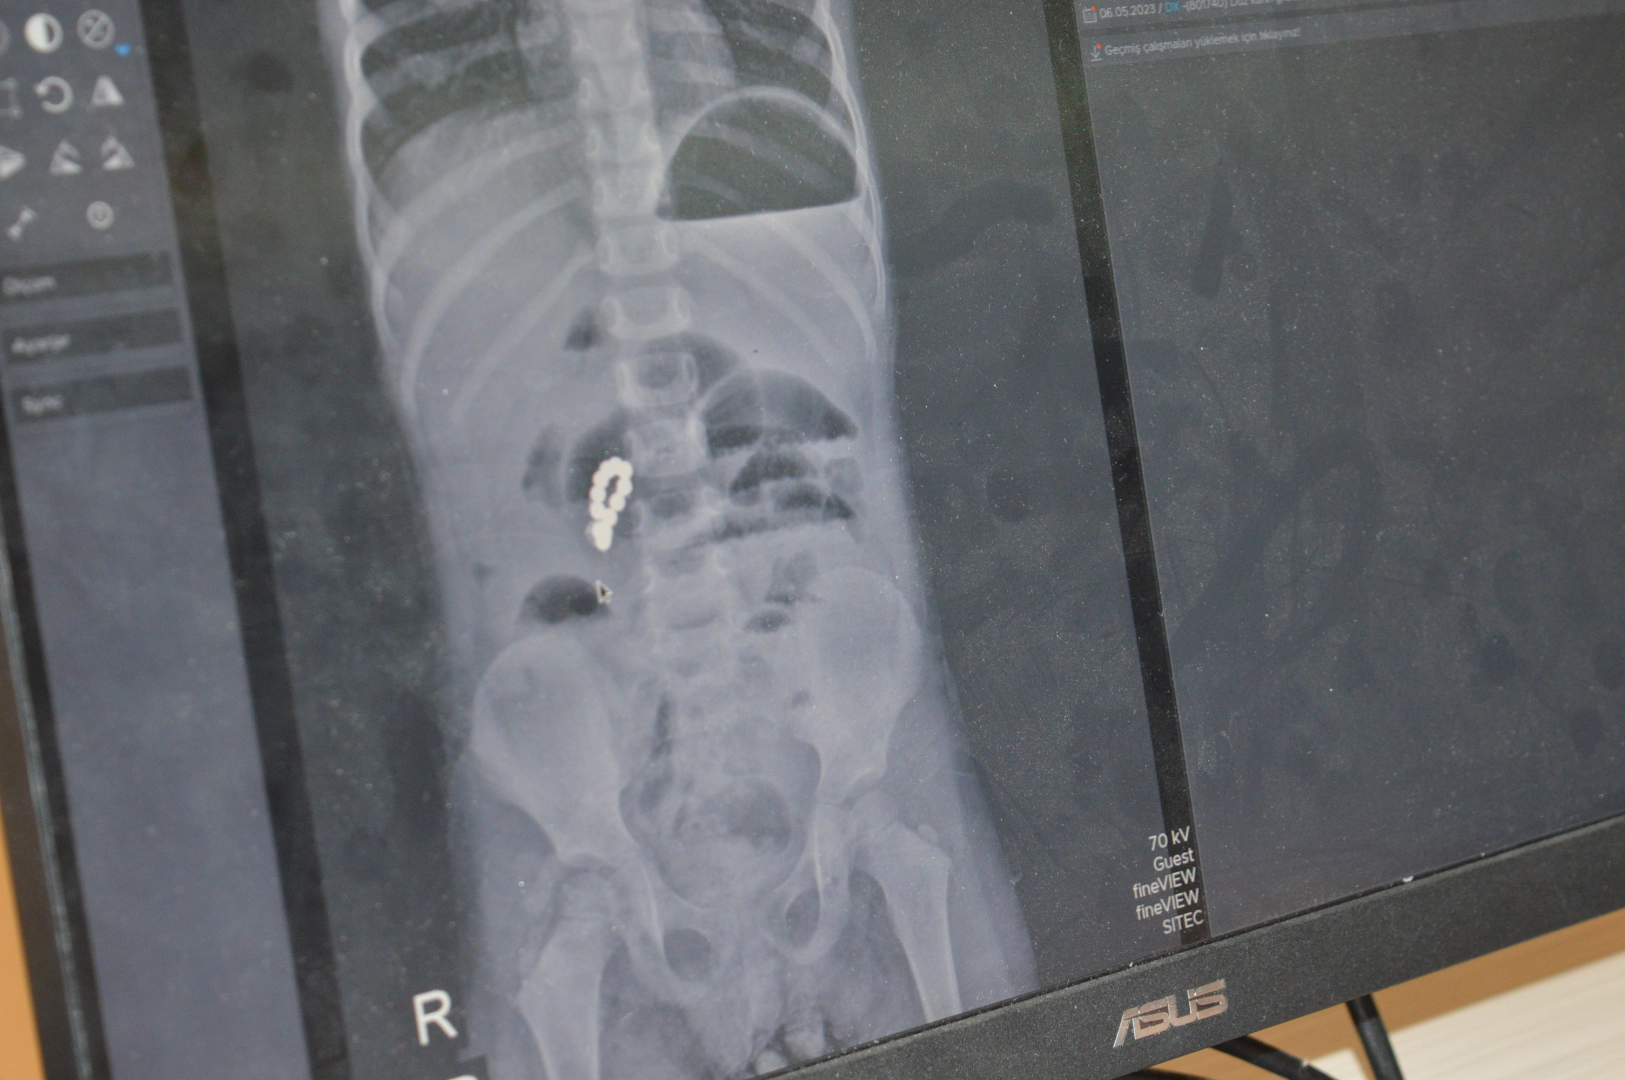

Nusaybin ilçesinde yaşayan Peker ailesinin kızları Eda Peker, evde oyun oynarken farklı zamanlarda yuttuğu mıknatıslar, bağırsaklarında hasara yol açtı. Peker’in mıknatıs yuttuğundan habersiz olan ailesi, karın ağrısı, bulantı ve kusma şikayetleriyle kızlarını Nusaybin Devlet Hastanesi’ne götürdü. Peker, gaz sıkışması şüphesiyle verilen ağrı kesicinin ardından eve gönderildi. Ancak Peker’in şikayetleri artınca yeniden hastaneye başvuruldu. Yapılan röntgen tetkiklerinde yabancı cisim yuttuğu tespit edilen Peker, Mardin Eğitim ve Araştırma Hastanesi’ne sevk edildi.

Burada Çocuk Cerrahi Uzmanı Op. Dr. Mürsel Haspulat tarafından ameliyata alınan Peker’in bağırsaklarında farklı zamanlarda yuttuğu 8 adet boncuk mıknatısın birbirine yapışarak bağırsakları deldiği ve tıkadığı belirlendi. Yaklaşık 3 saat süren ameliyatta bağırsaklar tek tek onarıldı, ameliyat sırasında tekrar röntgen çekilerek içeride başka parça kalıp kalmadığı kontrol edildi. Ağır geçen operasyonun ardından 6 gün yoğun bakımda kalan Peker, sağlığına kavuşarak taburcu edildi.

Ufak parçacıklı oyuncakların özellikle 6 yaşından küçük çocuklara verilmemesi gerektiği konusunda aileleri uyaran Op. Dr. Mürsel Haspulat, “Basit görünen bir oyuncak çocuğumuzu ölümle burun buruna getirdi. Bu tür mıknatıslar bağırsaklarda birleşerek hayati risk oluşturabiliyor. Aileler özellikle kış aylarında çocuklarını küçük ve parçalı oyuncaklardan, pillerden ve sert gıdalardan uzak tutmalı. 4 yaşındaki Eda, karın ağrısı ve kusma şikayetiyle geldi. Normalde basit bir şekilde apandisit ya da bağırsak düğümlenmesi diye düşünebildiğimiz bir vakaydı. Ama sonrasında röntgenlerini çekip hızlıca ameliyata almamız gereken bir durumla karşı karşıya kaldık. Çünkü ailenin de fark etmediği şekilde 2-3 hafta içinde tane tane mıknatıs parçalarını yutmuş ve bu mıknatıs parçaları bağırsakları birbirine yaklaştırarak düğümlenmesine ve delinmesine neden olup çocuğun bağırsaklarının tıkanmasına neden olmuştu. Ameliyatta öncelikli karmaşık tabloyu tek tek çözerek delinmiş bağırsak kısımlarını onardık. 3 saat boyunca uğraştık, devamında ameliyatın ortasında röntgen çektik tekrar içeride başka bir parçacık var mı diye kontrol ettik. Bir tane kalmıştı, onu da çıkartıp ameliyatı tamamladık. Fakat çok ağır bir ameliyat olduğu ve genel durumu da bozulmuş olduğu için çocuğumuz 6 gün boyunca yoğun bakımda yatmak zorunda kaldı. Yoğun bakımda 3’üncü gününde çok şükür beslenmeye başladı, daha sonra da servisi aldık. Şu anda taburcu ettik. Çok iyi ve şanslı bir vaka olarak sonuçlandı. Aileleri kesinlikle bu basit mıknatıslı oyuncaklar konusunda şiddetle uyuyorum. Farklı zamanlarda yutulduğunda ölümle burun buruna gelmesine neden olabiliyor. 6 yaş öncesi çocuklara parçacıklı oyuncaklar, madeni paralar verilmemeli. Bu ay çok fazla madeni para yutmalar geldi, yemek borusunda takılı kalıp yine ölümcül tablolara yol açabiliyorlar. Leblebi gibi parçacıklı gıdaları bile ailelerin 6 yaşından küçük çocuklara vermemeleri gerekiyor” diye konuştu.